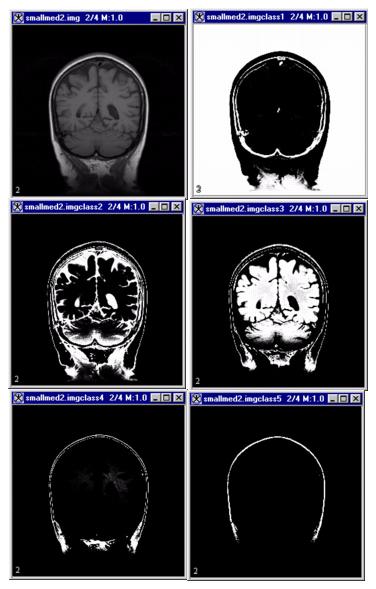

Figure 1. Fuzzy C-means algorithm processing

After entering the parameters for the algorithm in the Fuzzy C-Means dialog box (Figure 2), researchers select one of three choices for the output images:

Hard segmentation produces only one unsigned-byte output image. Pixels that do not meet threshold requirements are assigned the value of 0. The first class is assigned a value of 255/(nClass); the second class is assigned a pixel value of 2 x 255/(nClass), and so on. The last class has a value of 255.

Fuzzy segmentation produces one image, of the same type as the first source image, for every segmentation class. The membership function is scaled so that the minimum membership value scales to the first source image minimum value and the maximum membership value scales to the first source image maximum value. If boundary cropping is applied, all pixels outside the bounding box are assigned the minimum value of the first source image.